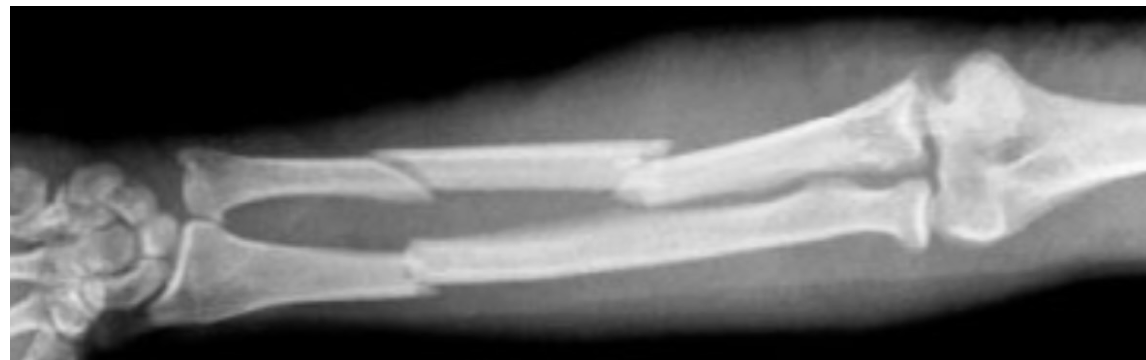

polsfractuur:

Wanneer conservatief?

Wanneer operatief?

Stabiel, niet-verplaatst → gips.

Instabiel

Intra-articulair

Slechte repositie

belangrijkste complicaties polsfractuur

Compartimentsyndroom

Carpaal tunnelsyndroom

CRPS

Zenuwschade